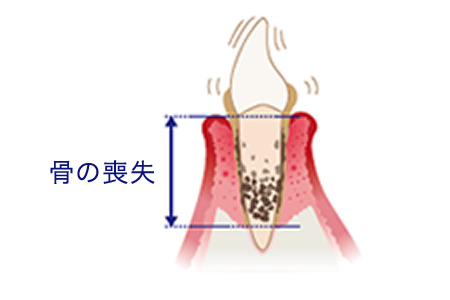

はじめは歯茎だけが腫れる歯肉炎に、そしてこの状態のまま放置すると、歯を支える歯槽骨が溶けてしまう歯周炎へと進行します。歯茎から血や膿が出たり、歯がぐらついて噛みにくく、口臭もひどくなっていきます。

歯周病はこうして進行します

歯槽骨が溶けて

後退してきます -

歯槽骨で歯を

支えられなくなります

歯周病の進行

中度歯周炎

歯周ポケットが形成され、歯石が深部まで付着し、歯を支える骨を半分くらい失っています。

歯肉炎〜軽度の歯周炎

歯を支える骨がなくなってきて歯がぐらつき、このまま放っておくと歯が抜けてしまいます。歯ぐきが下がる、膿がでるなどの症状もみられます。